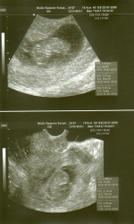

25.6. na utz dva váčky, zatím 1 srdíčko.

3.7. už nám tlučou 2 srdíčka. Je to moc krásný pocit. 🙂) Na OBI, jsem se rozloučila a byla odeslána ke svému gynekologovi. Ještě mě tam, ale čeká jedna kontrola v rizikové poradně pro vícečetné těhu, kterou mi pan docent nabídnul. Jsem ráda, že mají ještě zájem mě na Obi vidět. Jsou tam všichni moc hodní, jak sestřičky tak doktoři, opravdu jsem byla s jejich přístupem mooc spokojená.